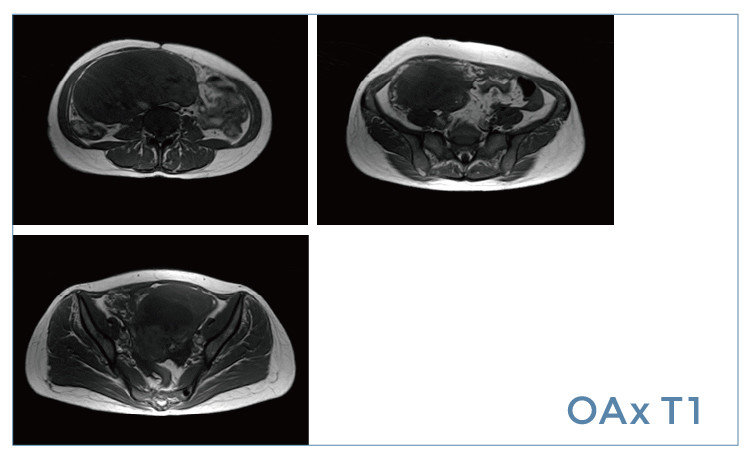

【朗润影像档案】磁共振影像病例分享(编号20190419)